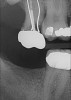

Fig 4. Patient No. 1 in 2016, with extrusion of tooth No. 15. Two different experiences in the same mouth, as shown in Figs 1–2 and Figs 3–4, underscore the unpredictability of extrusion.

Figure 4

Another consideration is mean vertical displacement of unhampered posterior teeth, which in some studies was minimal: 0.8 mm37 and 0.9 mm30 (Table 1). Yet, there could have been sites where the amount of extrusion was clinically relevant. When Lindskog-Stokland et al assessed the risk of over-eruption using 1 mm as a threshold, they stated there was an odds ratio of 3.3 that unimpeded molars would extrude 1 mm compared to opposed molars.30 Based on their calculations, however, it is unclear which patients with a missing molar are at risk of over-eruption (Figure 1 through Figure 4). Indeed, if susceptible individuals could be identified, then restorative therapy could be initiated to stabilize their occlusion (eg, tooth replacement). Furthermore, odds ratios can be highly misleading, and predictive values would provide clinicians a better perspective as to what percentage of sites may experience significant extrusion.41,42